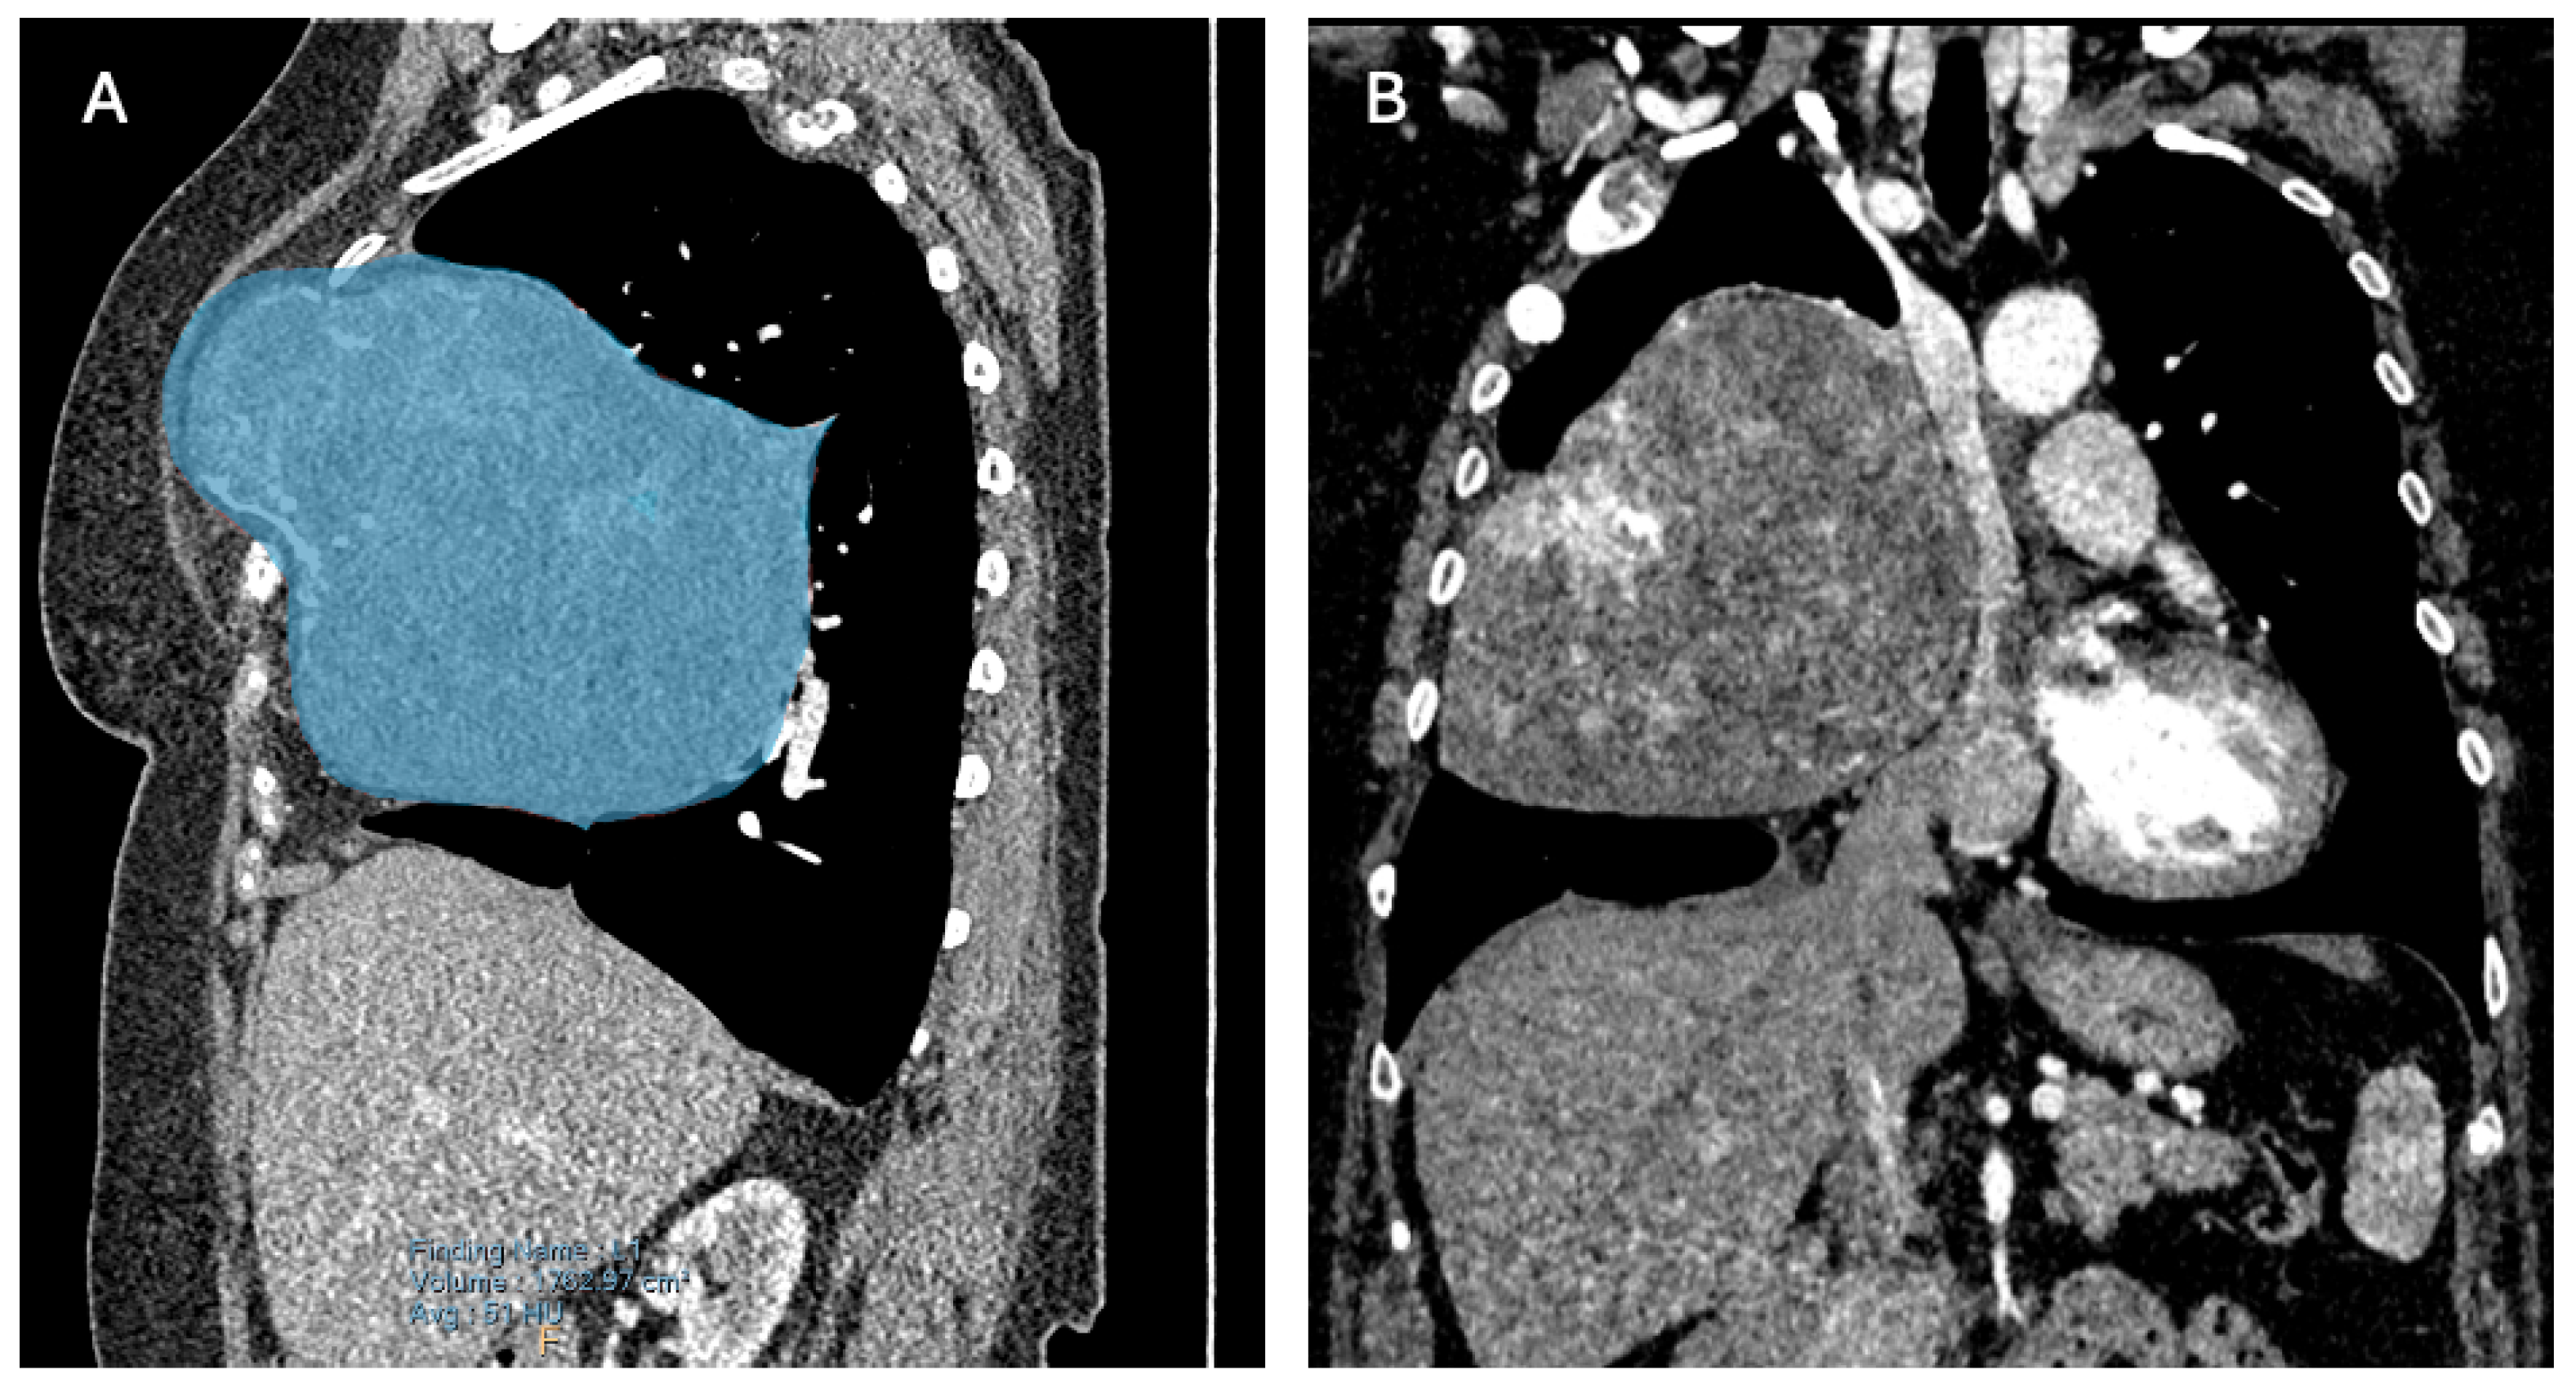

A computed tomography (CT) scan revealed three locations of FD: two minor lesions posterolateral in the second and third rib and one ventral in the third rib (Figure 2A), the latter being the most prominent lesion and responsible for the palpable extrathoracic mass (Figure 2B and Figure 3A). Its progression resulted in a mediastinal shift to the left (Figure 2C and Figure 3B) with compression of the superior caval vein and right atrium. Vascular displacement with compression of the right pulmonary artery was noticed, with dorsal displacement of the bronchus (Figure 2D).

Figure 3. (A) A right paramedian multiplanar reformation of the preoperative computed tomography (CT) scan. Blue overlay depicts the extrathoracic palpable FD and its continuity with the greater intrathoracic part. (B) A coronal multiplanar reformation of the preoperative CT scan. Visualization of the evident mass effect of the FD.